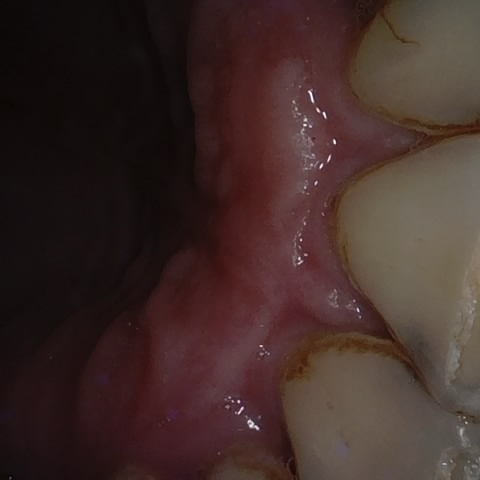

Annotated as "Good"